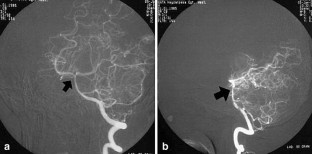

Brucellosis is a multisystem disease that may present with a large spectrum of clinical manifestations. Only five cases of intracranial aneurysm formation and/or subarachnoidal hemorrhage associated with brucellosis have been reported. In this paper, we take the opportunity to review these reports and present a new case of basilar artery aneurysm and subarachnoidal hemorrhage due to brucellosis.

Fig. 4